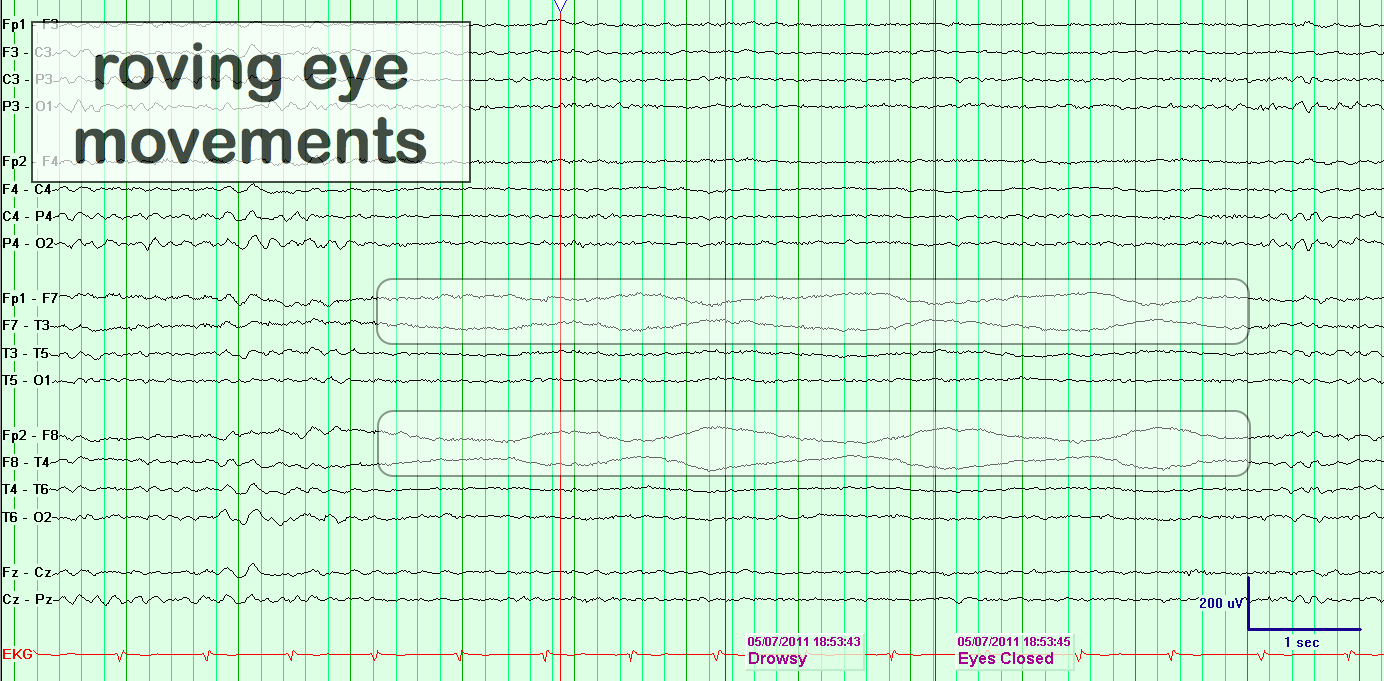

Roving Eye Movements

eegatlas-online.com

eegatlas-online.com

artifacts eye roving movements eegatlas online

Roving Eye Movements

eegatlas-online.com

eegatlas-online.com

eye roving movements artifacts eegatlas online